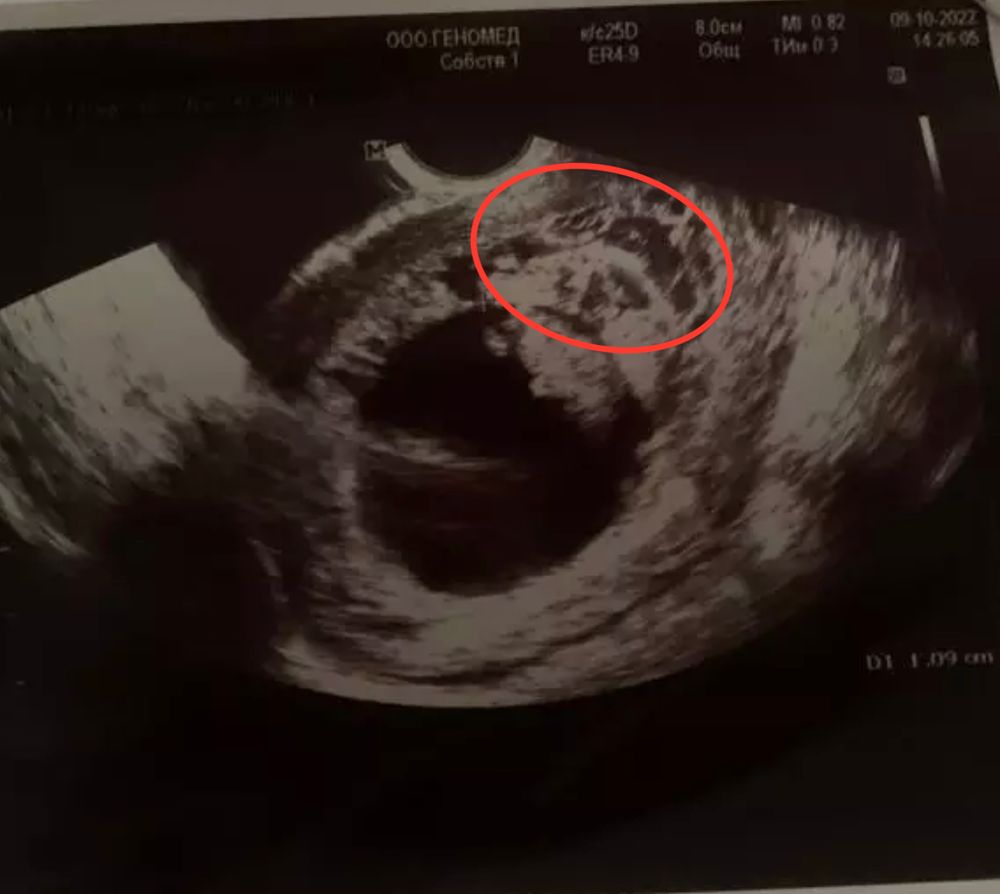

Пузырный занос. Узи. Помогите разобраться, если кто-то понимает🙏

Врач говорит похоже на начало частичного пузырного заноса.

10 неделя, беременность развивается, эмбрион жив.

кто как либо сталкивался с такой проблемой, прошу посмотрите узи!

Я не специалист, но похоже вот эта часть